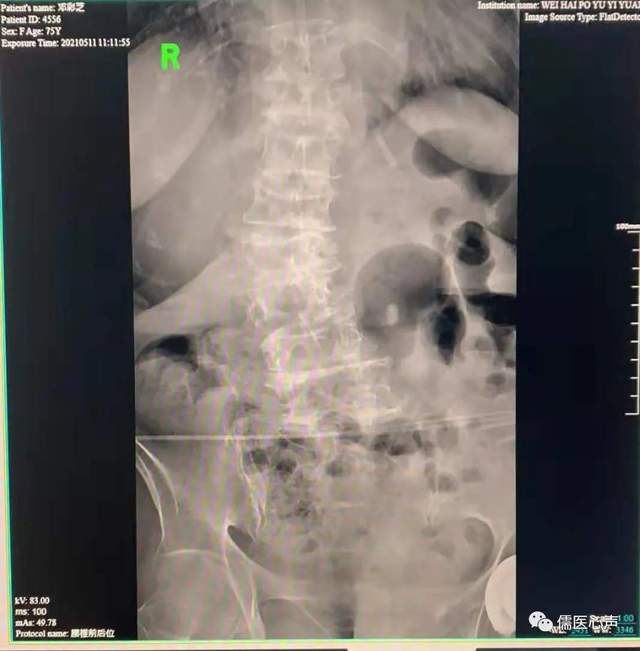

老年结构性脊柱侧弯侧位片。

病例三,近日出院病人,邓某,女,78岁,因”腰背部疼痛3月“于2021.5.11来诊并入院。患者往有腰椎压缩性骨折病史,现感腰背部疼痛,不能久坐久行,查体:脊柱腰段呈右凸侧弯畸形,双侧腰方肌肋缘、髂嵴、腰2/3/4横突尖附着点压痛(+),胸9至腰4椎体两侧广泛性压痛(+)。行相关部位针刀松解,并辅以针灸、中药外敷内服,经半月治疗,患者腰背疼痛逐渐缓解。